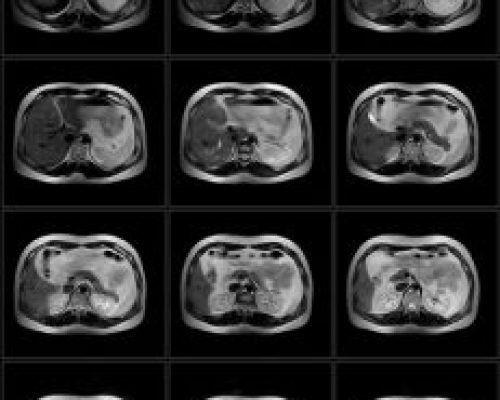

The PICA MRI system is our flagship product with its unique open architecture, advanced hardware platform and leading-edge clinical applications make it ideally suited for patient comfort, fast acquisition times and excellent image quality. The PICA has passed all ACR Accreditation requirements of 4 MRI modules: Head, Spine, Body and MSK. This accreditation also means that patient scans from PICA is approved for financial reimbursement by the US Government MEDICARE program as well as private insurance companies in the US.

- Whole Body MRI System

Supports a wide range of clinical applications, from brain to musculoskeletal scans, in a single, all-in-one platform.